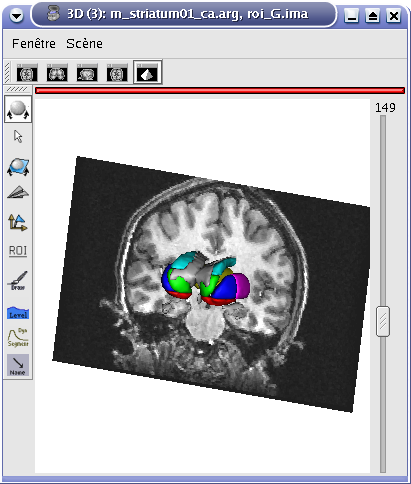

In the following example, 3 objects are loaded in Anatomist:

Object1 (O1): anatomy

Object2 (O2): regions of interest graph drawn from the anatomy. So these 2 objects are in the same referential.

Object3 (O3): nomenclature to associate colors to regions of interest according to their name. This object does not have to be put in a window. Link between names in the nomenclature and in regions of interest is done automatically by Anatomist.

These 2 objects are in the same coordinates system, so they will be placed in the same referential, that is to say they will have the same color circle (red by default).

Superimposing an anatomy and regions of interest¶